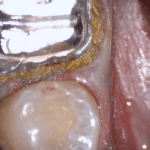

An old PFM crown warranted replacement due to open margins and recurrent decay. After the crown was removed, the margins were refined and the tissue was displaced with expasyl and retraction cord.